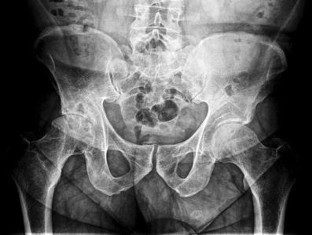

Pigmented villonodular synovitis (PVNS) is a rare, benign proliferative disease of the synovial tissue that affects a single joint or a tendon sheath. Data from the literature present only a few cases of multifocal PVNS. This paper presents multifocal PVNS in the adult. This disease can affect bilateral shoulders, hips and knees. The diagnosis may be delayed by the slow evolution of the disease (up to ten years); some patients may be seen with late-stage degenerative joints, serious complications, painful and functionally uncompensated, with significant locomotion deficit. PVNS requires a radical treatment with prosthetic arthroplasty associated with synovectomy. Complex imaging (X-Rays, magnetic resonance imaging (MRI), ultrasound) and macroscopic appearance of the lesions during surgery confirms the clinical diagnosis of multifocal PVNS with secondary bone lesions. Histology marks the final diagnosis of multifocal PVNS. The postoperative results are good, with recovery in functional parameters of the joints with endoprosthesis.